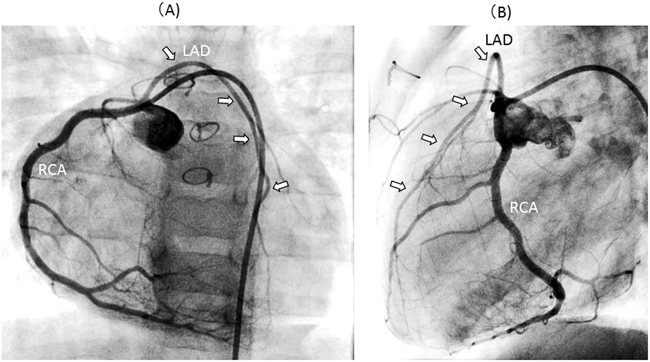

ファロー四徴において冠動脈異常が合併する頻度は5~12%と報告されている.冠動脈異常の内訳は以下のようになる.前下行枝右冠動脈起始右室流出路腹側走行(AAOLAD-AF)(58%)(Fig. 10),右冠動脈の左冠動脈起始(17%),右冠動脈の左前下行枝起始(6%),単一右冠動脈(R2-A)(3%),また太い円錐枝(conal branch)の右室流出路走行(17%)である69, 70).いずれも血行動態的上の問題はないが,主要な冠動脈が右室流出路(肺動脈弁輪の下方平均10 mm)を横切ることから,心内修復術の際に右室流出路拡大が必要な症例において手術手技を困難にすることがある.心エコー検査にて右室流出路前面を横切る冠動脈が疑われた場合には,大動脈造影やCT等で冠動脈の走行を確認しておく必要がある.

Fig. 10 Anomalous aortic origin of the left anterior descending coronary artery from the right coronary artery in a patient with tetralogy of Fallot

(A): Selective right coronary arterial angiogram from the anteroposterior view: LAD (arrows) originates from the RCA.(B): Lateral view of the same selective right coronary arterial angiogram: LAD (arrows) runs on the anterosuperior side of the right ventricular outflow tract.LAD: left anterior descending artery; RCA: right coronary artery.